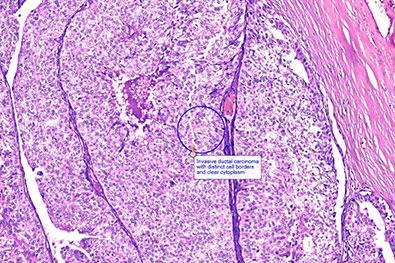

Extensive Cancer Databases

We maintain comprehensive digital libraries for major cancers, including:

Breast Carcinoma

Each dataset includes a large number of cases, including benign and normal counterparts, providing rich AI training material.